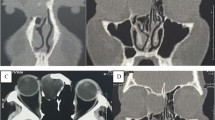

Axial (a) and coronal (b) CBCT images of a typical pars flaccida cholesteatoma in the left temporal bone extending in Prussak’s space with medial displacement and erosion of the ossicular chain (asterisk in a, b). Notice the erosion of the scutum (white arrow in b) and the presence of a tympanostomy tube. Axial (c) and coronal (d) CT of a typical pars tensa cholesteatoma (asterisk in c, d), originating in the lower and posterior part of the middle ear, extending in the tympanic sinus (black arrowhead) and facial recess (black arrow). There is lateral displacement of the ossicular chain and erosion of the incudostapedial joint (white arrowheads in c, d) which should be visible on this coronal slice. Both these lesions and CC are often undiscernible on MRI